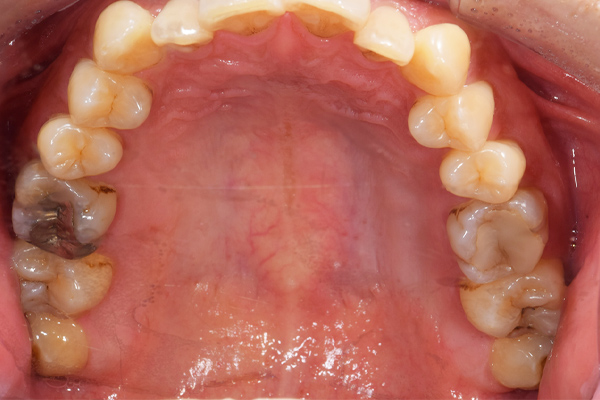

検査時のレントゲン写真です。

下顎の親知らずは右下のみはえています。まっすぐはえていますが、前の歯よりも低い位置にあるので、磨くのが難しそうです。舌側の歯茎がかぶっているのがみてとれます。

上顎の親知らずは頬の方を向いてはえています。こういうった親知らずはやはり磨くのがとても難しいです。

上顎の親知らずの抜歯のBefore/Afterです。抜歯時間は10分です。上顎の抜歯はほとんど腫れることもないです。リスクとしては一番最初の症例のように上顎洞への穿孔です。ただし、穿孔したとしても、鼻をつよくかむなどせず、安静にしていれば、しっかり回復しますので安心してください。抜歯費用は約1,700円(保険適応)

です。